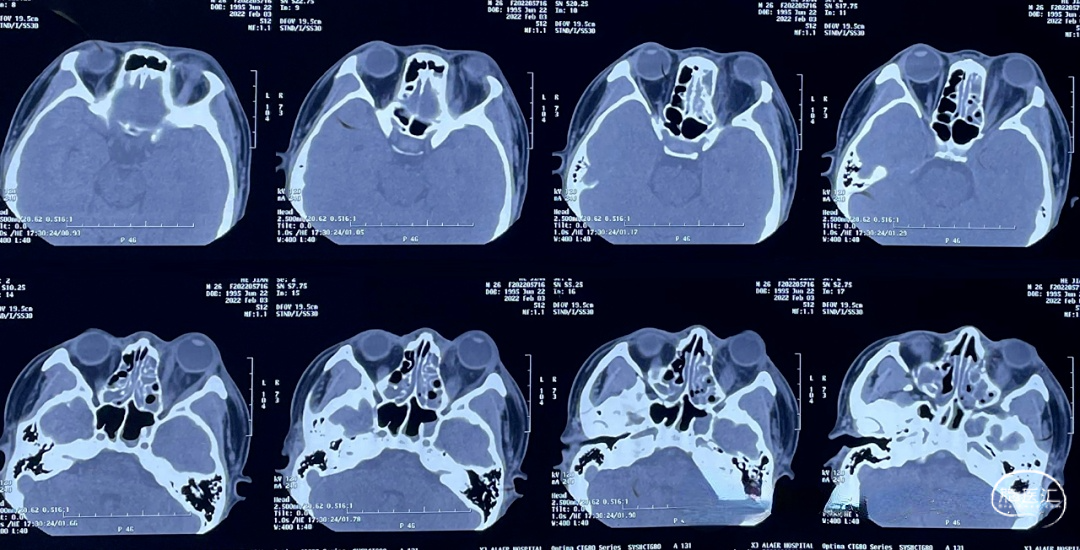

2022.02.02CT:多组鼻窦炎,筛窦为主,感染累及左侧眼眶,眶内组织肿胀;邻近额叶脑组织大片水肿,考虑感染波及颅内

2022.02.03CT:鼻窦感染范围扩大,眶内组织水肿加重,眼球凸出。